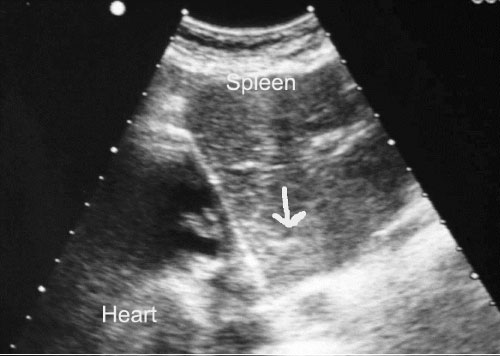

His chest radiograph demonstrated r right sided cardiac apex. His focused assessment with sonography in trauma (FAST) examination revealed the presence of fluid in Morison's pouch in the left upper quadrant (Figure 2), contusion over the spleen in the right upper side (Figure 3), but no free fluid in the pelvis or pericardial fluid. His computed tomography scan (CT) demonstrated fluid around the liver without solid liver organ injury and multiple splenic contusions (Figure 4).

Figure 3: FAST examination shows hyperechoic areas on the spleen from a contusion (arrow). View Figure 3